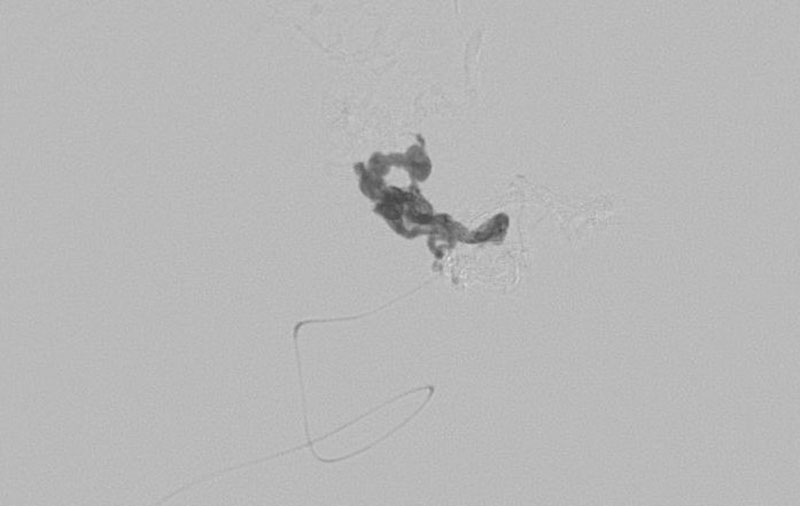

No.1620 手術前

No.1620 手術中

No.1620 手術後